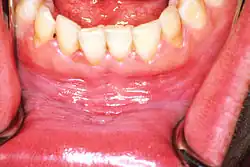

![]() | |

| Leukoplakia on the inside of the cheek | |

Homogeneous leukoplakia (also termed "thick leukoplakia")[2] is usually well defined white patch of uniform, flat appearance and texture, although there may be superficial irregularities.[2][9] Homogeneous leukoplakia is usually slightly elevated compared to surrounding mucosa, and often has a fissured, wrinkled or corrugated surface texture,[2] with the texture generally consistent throughout the whole lesion. This term has no implications on the size of the lesion, which may be localized or extensive.[2] When homogeneous leukoplakia is palpated, it may feel leathery, dry, or like cracked mud.[2]